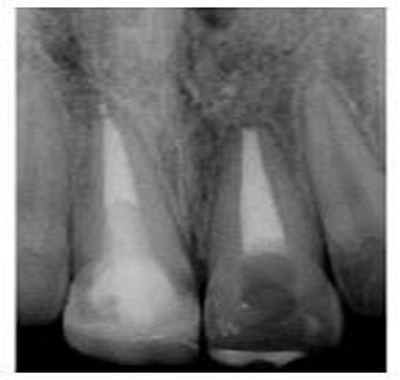

切端則采用透明樹脂,最后使用釉質(zhì)樹脂(Amaris, VOCO, Cuxhaven, Germany)。21的樹脂修復采用類似的方式。修復初步成型,拋光,恢復干燥牙釉質(zhì)的顏色。攝片顯示樁在根管內(nèi)位置合適(圖15)。最后一次復診精修、拋光充填體,完成治療。